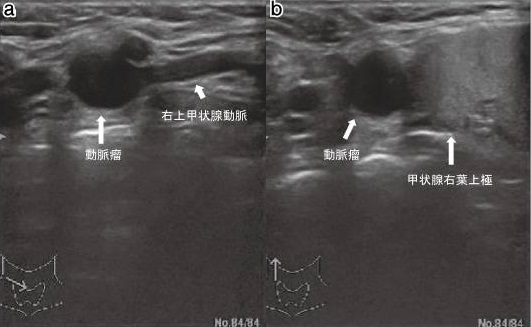

大動脈留だけではありません。動脈硬化による動脈瘤は、甲状腺を栄養する動脈にも起こります(日血外会誌 15:517-519,2006)。上甲状腺動脈瘤、下甲状腺動脈瘤で、これまでに40例未満の報告しかありません。大きさは0.8~6.2cmと様々で、大きさと破裂の有無とは関連しません。

甲状腺動脈瘤以外の末梢動脈瘤は、血栓塞栓症が多く、破裂は稀とされます。しかし、甲状腺動脈瘤で血栓塞栓症をおこした報告はありません。甲状腺動脈瘤報告例で、破裂の割合は下甲状腺動脈瘤58.3%、上甲状腺動脈瘤25%、破裂瘤の20%は死亡しています。

甲状腺動脈瘤で破裂が多いメカニズムは不明です。 破裂前に見つけて無症候性(症状が無い)でもコイル塞栓術、あるいは外科的切除(甲状腺の一部を同時切除もあり)を早急に行う必要があります(内分泌甲状腺外会誌 31(3):243-246,2014)。元々、甲状腺手術予定があるなら、同時に切除もあり得ます。

甲状腺動脈瘤が破裂した場合、

- 痛みを伴う急速な頚部腫大(頸部血腫)

- 気管圧迫による著明な呼吸困難

- アッと言う間に失血性ショック

甲状腺腫瘍を穿刺吸引細胞診する際、甲状腺動脈の外膜を傷付けて仮性動脈瘤が発生する事があります。動脈硬化した硬くて脆い所が動脈瘤に成り易いとされます。破裂すると命にかかわるため、コイル塞栓術、あるいは外科的切除(甲状腺の一部を同時切除もあり)を早急に行う必要があります。[J Ultrasound Med. 2004 Dec;23(12):1675-8.]